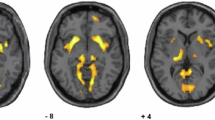

The lethality of the last suicidal act (as measured with the first part of the RRRS) was negatively correlated with the left (r = −0.35, n = 73, p = 0.002), and right accumbens volume (r = −0.41, n = 73, p < 0.0005). Scatterplots summarize these results (Fig. 1). Removing two outliers did not modify the results. After controlling for the effect of sample, gender, age, intracranial volume, BIS scores, NART scores, bipolar status and medication using partial correlations, these associations remained significant. The impulsivity score on the BIS did not correlate significantly with accumbens volumes when controlling for sample. HAMD negatively correlated with the right pallidum (r = −0.35, n = 253, p = 0.002). BDI and SIS did not correlate with any subcortical volumes.